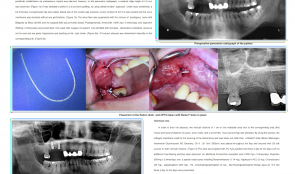

Objectives: To reduce morbidity of lateral window sinus grafting using a minimally invasive (flapless) surgical technique with piezoelectric osteotomy and hydraulic pressure from the same instrument. The grafting material was Bio-Oss collagen, a well-documented material for regenerating bone in the maxillary sinus. Methods: Five patients in the private clinic of the author were randomly selected for the study, and cone-beam CTs (CBCTs) were taken. Patients with at least 3mm of bone from the crestal ridge to the floor of the sinus and a width of more than 6mm were recruited. In order to prevent resorption of the crestal bone, a flapless approach was used, with tissue punches. Preparation of the osteotomy and fracture of the floor of the sinus was performed using the Intra Lift Kitä/®. Hydraulic pressure was applied using the same instrument to lift the Schneiderian membrane. The integrity of the membrane was confirmed by the Valsalva test. Bio-Ossä/® collagen block was soaked in saline and cut in to pieces, then each piece was introduced into the osteotomy using tweezers and TKW5TM/®, beneath the elevated membrane. The diameter of all implants was 4.5mm. The osteotomy was undersized by about 1mm to ensure that all implants had good primary stability. They were covered with healing abutments on the day of surgery and IOPA were taken. After a 6-month‘ healing period, implants were progressively loaded with composite crown before final fabrication of the definitive crowns. Further CBCTs were taken after 6 months to confirm bone growth in the sinus. Results: Membrane perforation was observed in one patient in whom the implant was placed in the upper second molar region due to inadvertent slippage of TKW4TM/®. However no complications were reported. Newly formed bone along the implant was recorded in all cases, and average bone height gain was about 5mm. Conclusions: Although there was a perforation of the sinus membrane in one case, no complications occurred and there was bone gain and osseointegration of the implants. Given the small sample size of five cases, it seems that the minimally invasive approach using xenograft Bio-OssTM/® collagen as the sole grafting material, results in an average bone gain of 5mm and osseointegration of implants. -